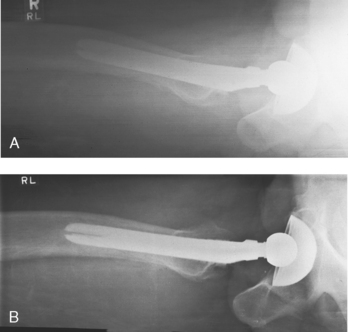

• The Ferlic swimmer’s filter is a collimator-mounted filter created to improve imaging of the lateral projection of the cervicothoracic region (swimmer’s technique) (Fig. 2-8), but it is also used for the axiolateral projection of the hip (Danelius-Miller method) (Fig. 2-9). The Ferlic shoulder filter, also a collimator-mounted filter, is designed specifically to image the shoulder in both the supine and upright positions.

Fig. 2-9 A, Axiolateral projection of hip (Danelius-Miller method) without compensating filter. B, Same projection with Ferlic swimmer’s filter. Note how acetabulum and end of metal shaft are seen on one image.